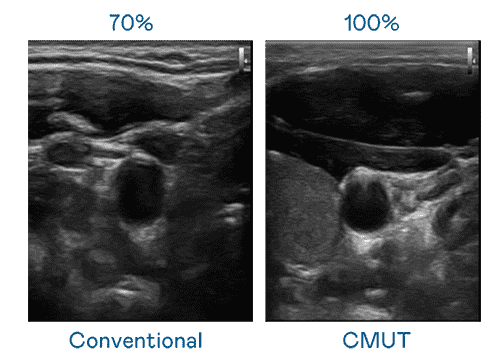

CMUT 技术是一种用电容式微机电元件来产生超音波讯号的技术。。与传统 PZT 压电式技术相比,,,CMUT 频宽增加 30%,,,,更宽频的超音波讯号让影像解析度大幅提升,,,,是实现高影像品质医疗超音波扫描、、、、促进精准医疗发展的关键技术。。。。

大频宽带来超清晰影像

超音波影像的解析度高低,,,,首先取决于探头能发出的讯号频宽。。z6尊龙 CMUT 可提供高清晰的超音波讯号,,,,提供高频宽、、高灵敏度、、、影像纹理细节更高的超音波影像,,协助医护人员缩短影像判读时间及利用精准的医疗影像进行诊断。。。。